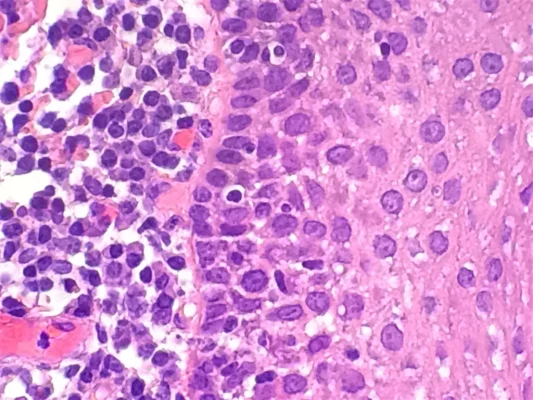

What is H&E Staining?

H&E staining, also known as Hematoxylin and Eosin staining, is a commonly used staining technique [...]